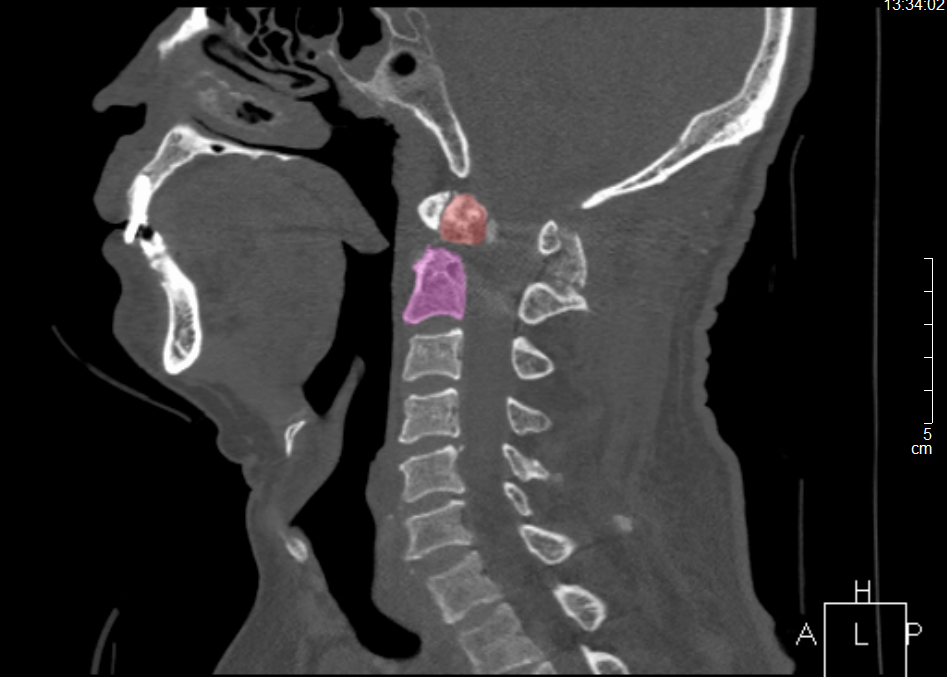

王先生術(shù)前CT

今年8月下旬,王先生因雙上肢酸痛、麻木難忍一月余才來就診。X線檢查顯示,王先生樞椎陳舊性骨折不愈合。脊柱創(chuàng)傷外科醫(yī)療團(tuán)隊(duì)詳細(xì)評(píng)估認(rèn)為,患者寰椎樞椎極度不穩(wěn)定,隨時(shí)可能截癱進(jìn)而危及生命,需盡快手術(shù)治療。此時(shí),王先生毅然選擇手術(shù),解決“折磨”了自己30余年“心頭大患”。